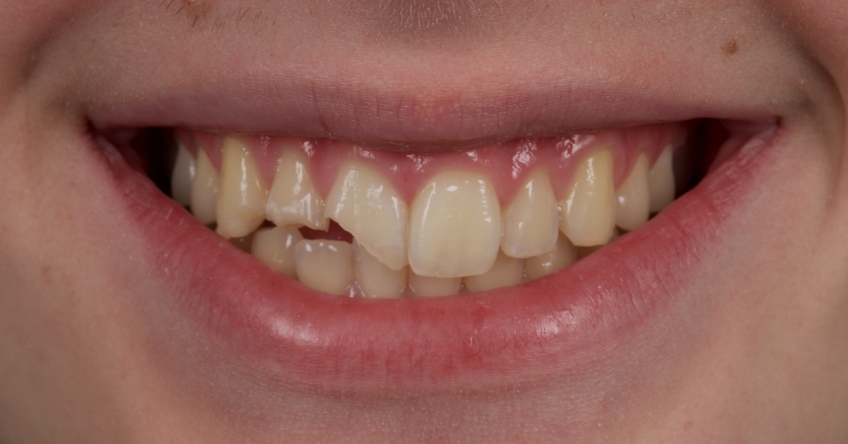

This 21-year-old male presented with an uncomplicated enamel-dentin fracture of the upper right central, lateral incisor, and canine following a fall.